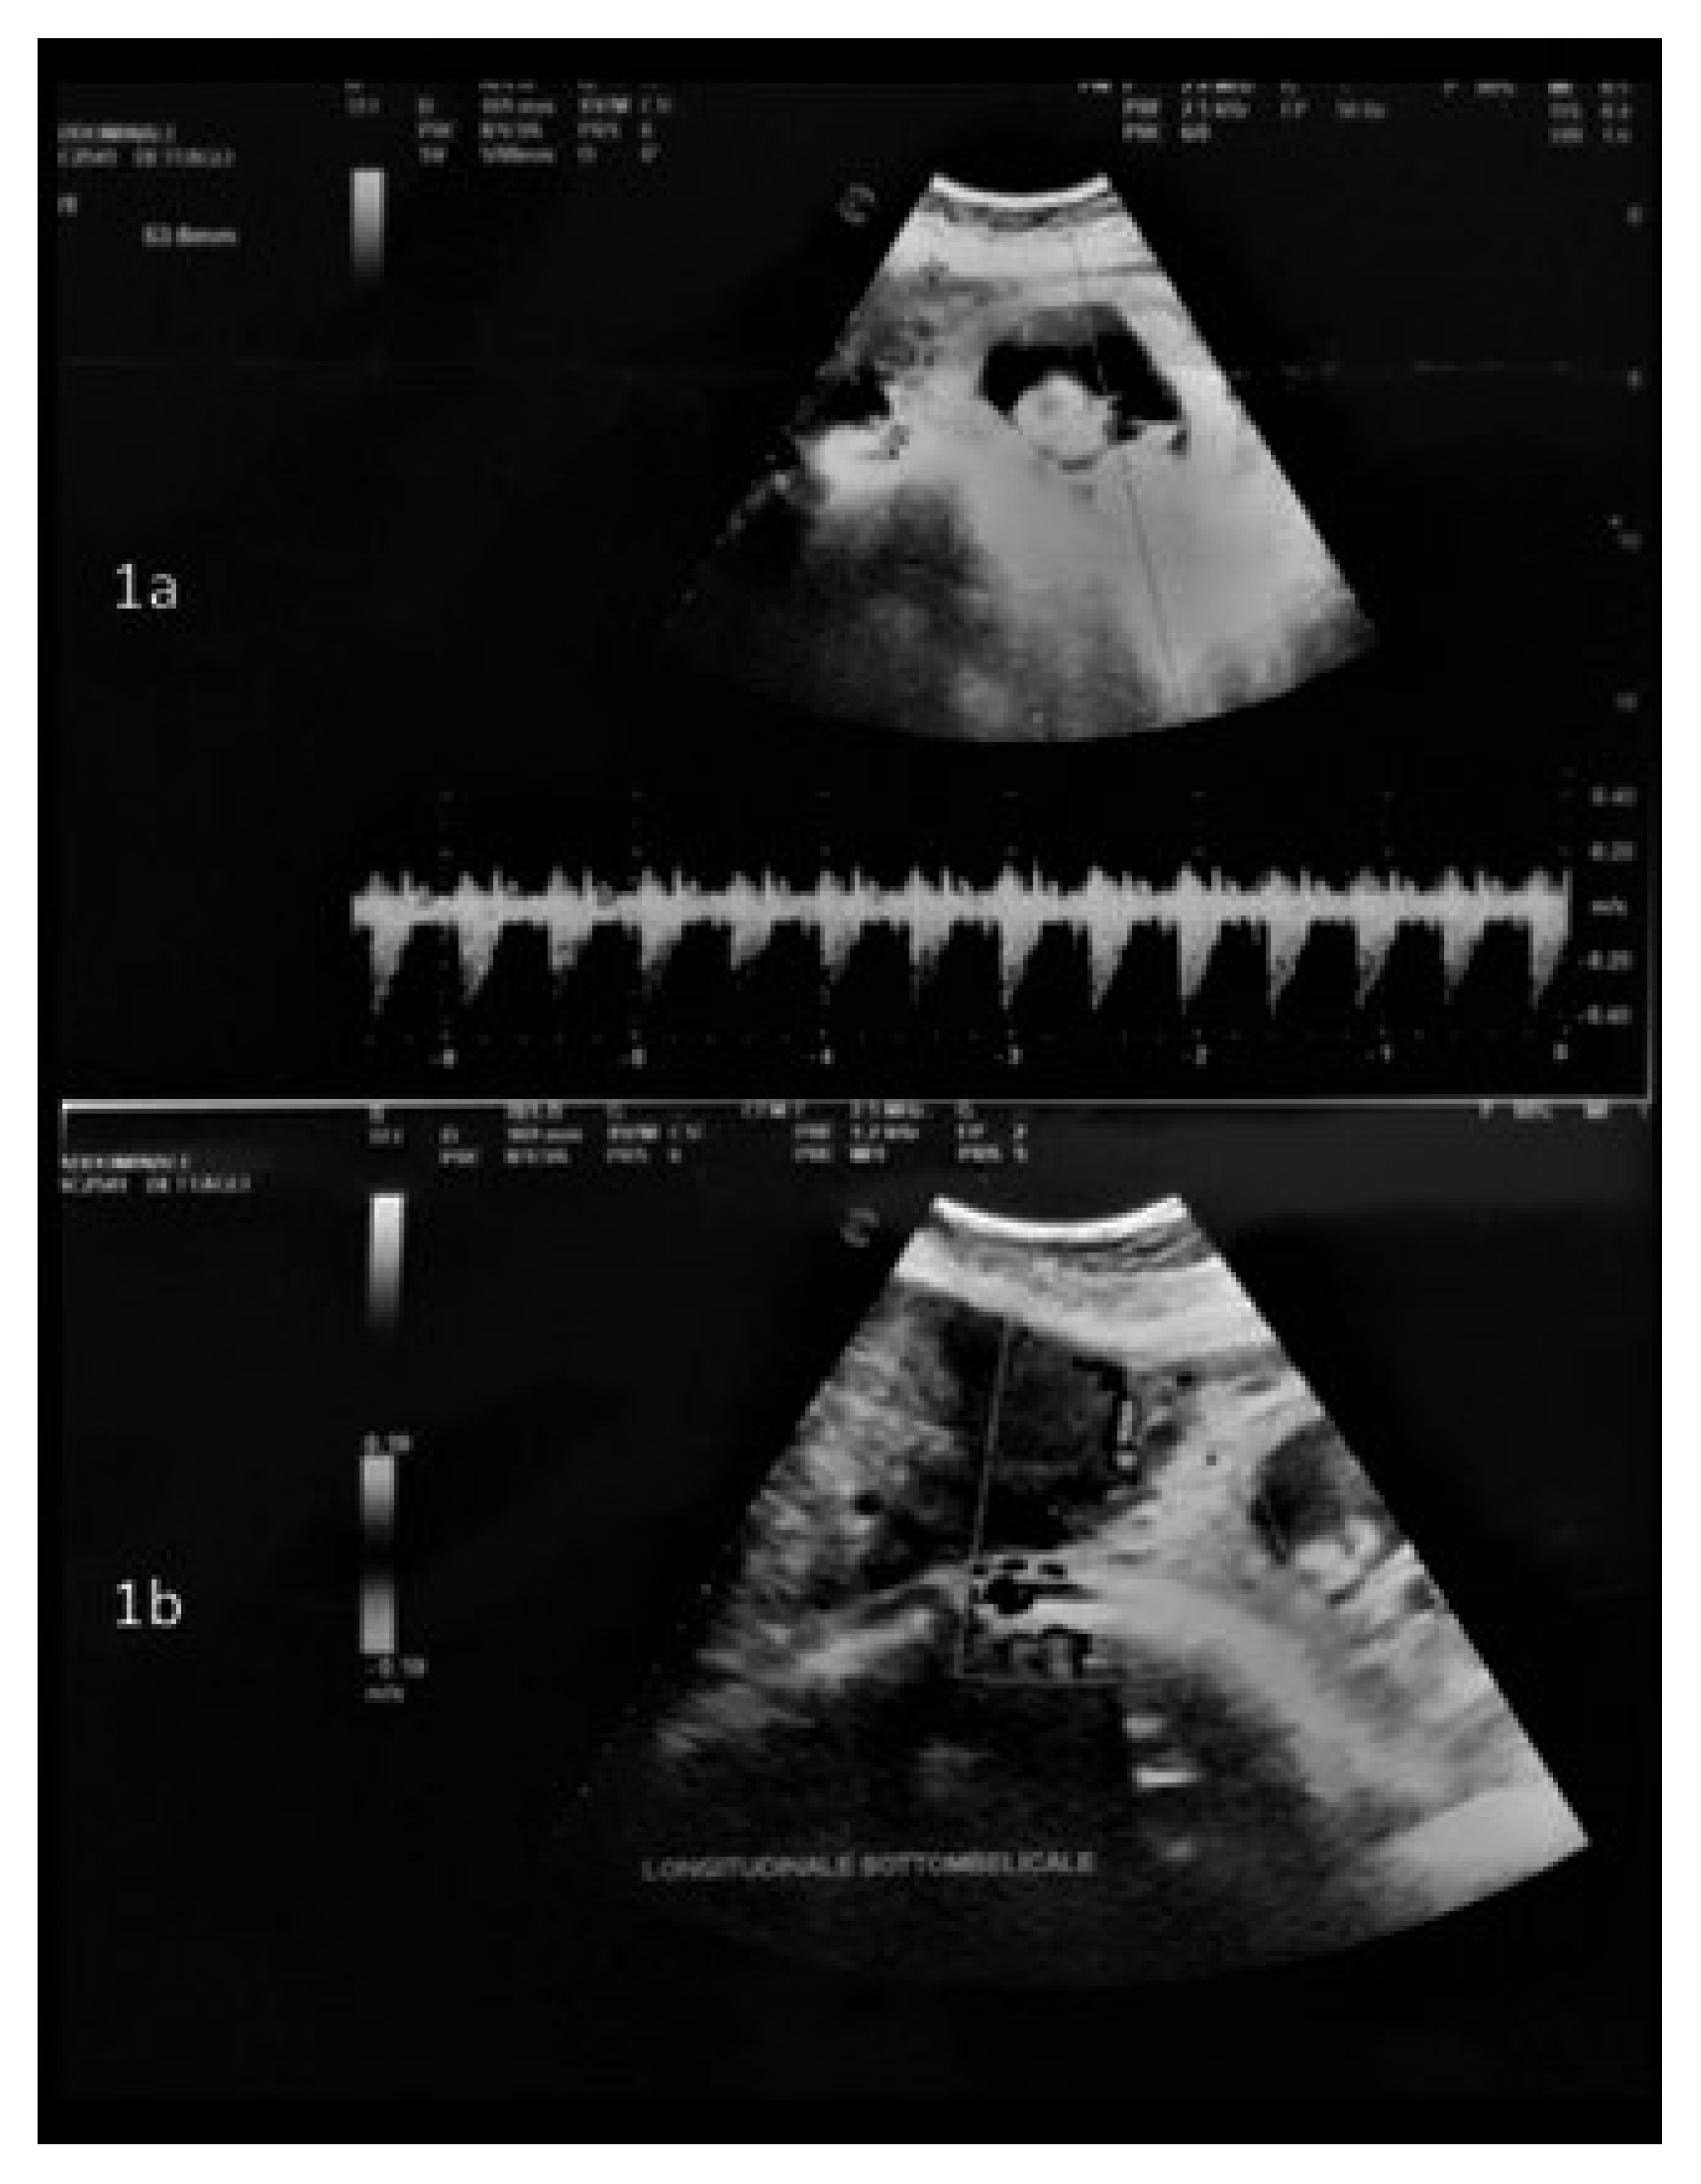

- Moruzzi, M.C.; Moro, F.; Bolomini, G.; Macchi, C.; Cavaliere, A.F.; Fagotti, A.; Scambia, G.; Testa, A.C. Intraoperative ultrasound assistance during myomectomy in pregnant woman. Ultrasound Obstet. Gynecol. 2020, 55, 840–841. [Google Scholar] [CrossRef] [PubMed]